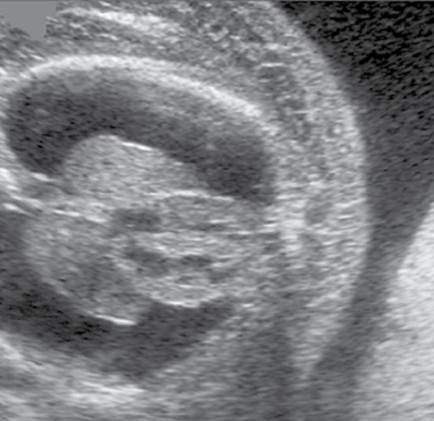

Spaulding’s sign